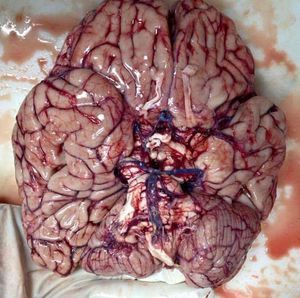

The base of the brain is a masterpiece on its own! This unique photo shows the inferior surface of the brain, primarily the brainstem, upper portion of the spinal cord, circle of Willis, and both right and left hemispheres. Of you recall from anatomy classes, The brain is composed of 3 main structural divisions: the cerebrum, the brainstem, and the cerebellum. At the base of the brain is the brainstem, which extends from the upper cervical spinal cord to the diencephalon of the cerebrum. The brainstem is divided into the medulla, pons, and midbrain and posterior to the brainstem lies the cerebellum. The midbrain — the uppermost part — has fibers that connect the brain stem to the cerebrum and cerebellum; this area is very important in the control of skeletal movements. The pons, which lies between the midbrain and medulla oblongata, relays sensory information between the cerebrum and cerebellum. The medulla oblongata contains centers for the control of breathing and cardiovascular function. The cerebellum on the other hand regulates muscle tone, coordinates movement and helps maintain posture and balance. It does not initiate movements, but is responsible for their smooth and balanced execution, for maintaining muscle tension and making movements work together in complex action such as walking. It comprises approximately 10 percent of the brain’s volume, contains at least half its neurons and is connected to the brain stem via three major bundles of input and output fibers called peduncles. Art and creation at its finest.